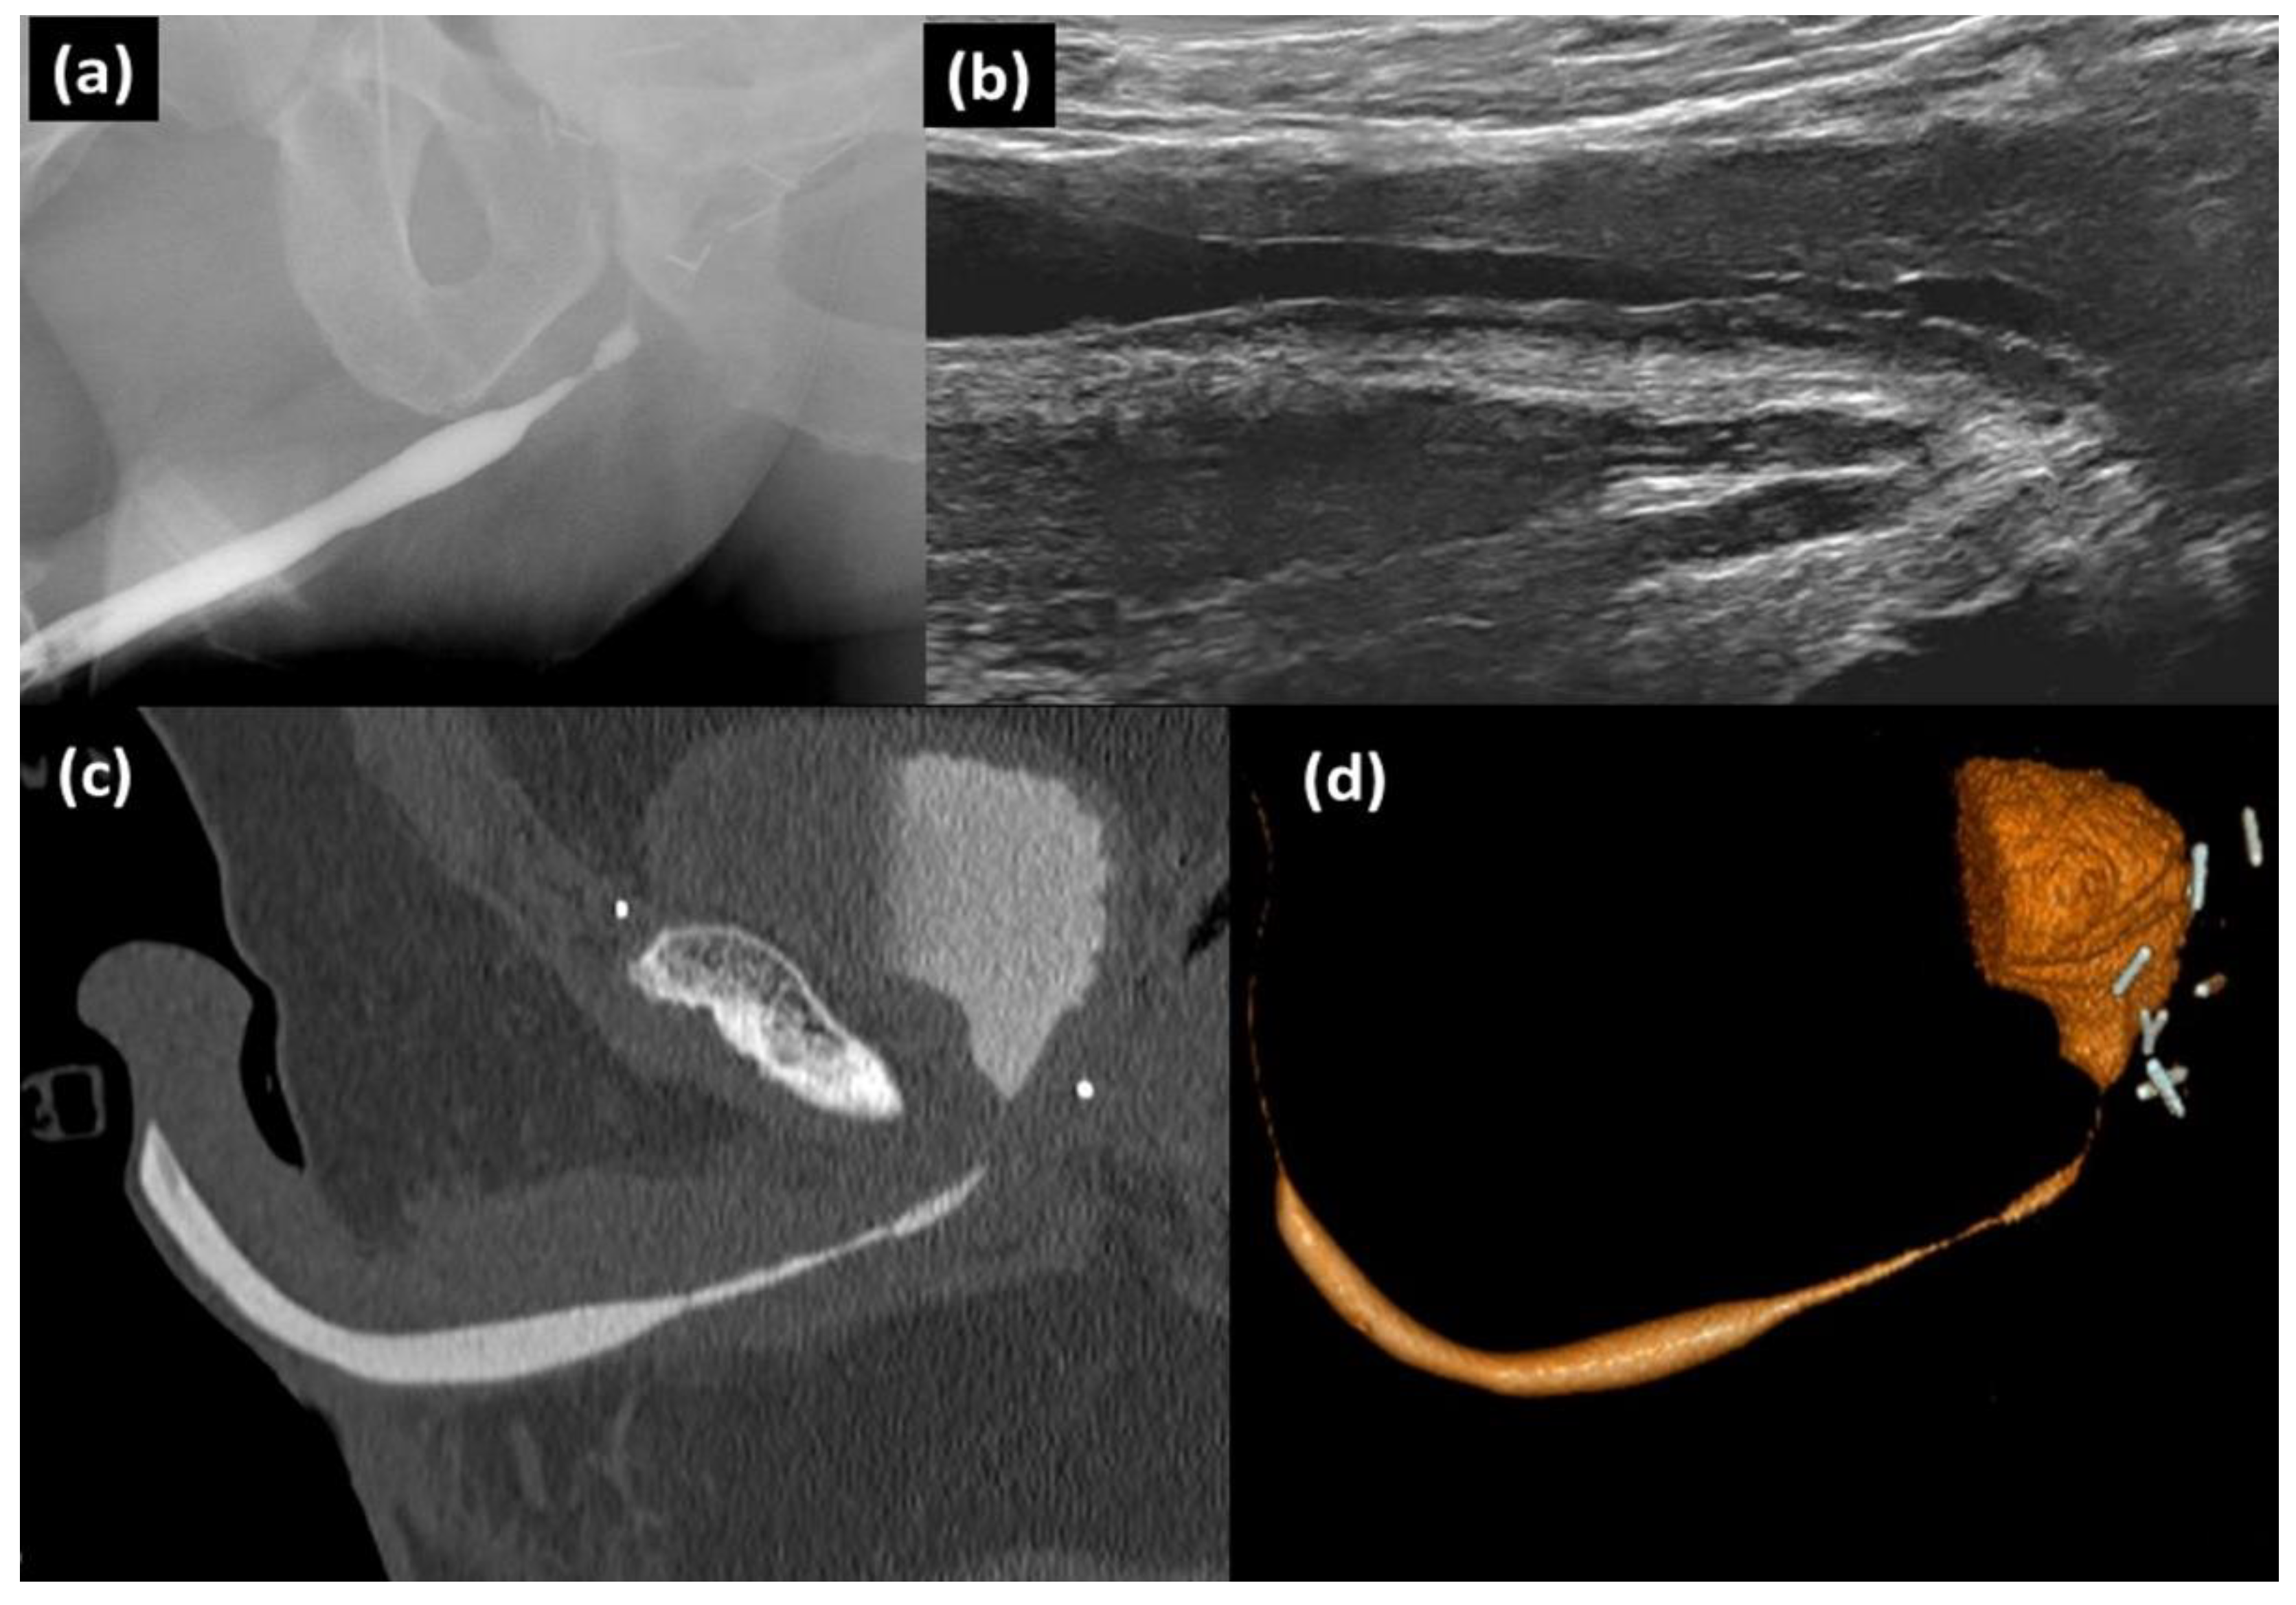

Figure 3. Patient with bulbar stenosis of a length underestimated by urethrography: (a) RUG showing 1.7 cm stenotic bulbar segment with a drastic reduction in the caliber of the urethral lumen; (b) retrograde sonourethrography (RSUG) showing the stenotic bulbar segment and surrounding spongiofibrosis, measuring 3.1 cm in total; (c) CT-RUG showing stenotic bulbar segment measuring 3.2 cm in length (measurement similar to RSUG and greater than RUG). (d): 3D CT-RUG image.

Of the 11 cases with anterior urethral stenosis, most were located in the bulbar urethra (n = 7) and the rest in the penile or penobulbar urethra (n = 4). All the cases had previous urethral manipulation: radical retropubic prostatectomy (n = 2), urethroplasty (n = 2), transurethral resection of the prostate (TURP) (n = 2), internal urethrotomy (n = 2), urethrocystoscopy (n = 2) and urinary catheterisation (n = 1). In the 2 cases with urethroplasty the focal strictures between the tortuous lumen of the plasty were only revealed by CT-RUG (Figure 2). In the remaining 9 cases the mean length of the stricture was 2 ± 0.7 (SD) cm (range, 1.1–3.1 cm) on urethrography, 2.8 ± 0.9 (SD) cm (range, 1.8–4.2 cm) on RSUG and 2.9 ± 0.9 (SD) cm (range, 1.9–4.3 cm) on CT-RUG. An underestimation of the stricture length was found on RUG when compared to RSUG and CT-RUG (p = 0.008) (Figure 3 and Figure 4).

The introduction of contrast in RUG was first done using clamp devices coupled to a syringe (Knutsson clamp, Brodney clamp). These were replaced by the McCallum technique using a Foley catheter, but the drawbacks of this method are that it can cause pain on inflation of the balloon and it is not useful in cases with urethromeatal alterations, nor can anesthetic gel be used or contrast introduced very accurately (risk of balloon leakage) [2,6]. The technical difficulty with performing CT-RUG with a Foley catheter may be the cause. However, there are only 2 studies in which CT-RUG and CT-VCUG were done simultaneously to evaluate anomalies of the posterior urethra [4,11]. The first, by Kassaby et al. [4], evaluated urethral distraction defects after blunt pelvic trauma in 21 males; the bladder was filled through a suprapubic catheter (with which the patient was fitted) to achieve a full bladder sensation, after which they performed retrograde infusion of contrast (technique not specified) and combined retrograde and voiding CT. In the second study, Zhang et al. [11] evaluated posterior urethral strictures in 21 males; the bladder was filled with contrast via an infusion system connected to the suprapubic catheter (with which the patient was fitted) and the anterior urethra using a Foley catheter (after inflating the balloon with 2–3 mL of serum in the fossa navicularis), after which they performed the combined retrograde and voiding CT (3 s after the patient started to void). To our knowledge, the present study is the first to evaluate the utility of CT-RUG for stenosis of the anterior urethra (bulbar or penile). It reports an accuracy similar to RSUG and greater than RUG for measuring the length of strictures. In the 2 cases with urethroplasty the CT was also better than the other techniques for visualizing stenosis in the tortuous track of the plasty. The advantage of CT over urethrography is that it can evaluate periurethral structures and locate stenosis with greater anatomical accuracy. The advantage over RSUG is that CT has a complete field of view (FOV), whereas measuring stenotic segments longer than 3 cm means resorting to a panoramic ultrasound image, which may distort the measurement as it is particularly operator-dependent (Figure 4).